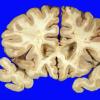

Subcortical Arteriosclerotic Encephalopathy (6)